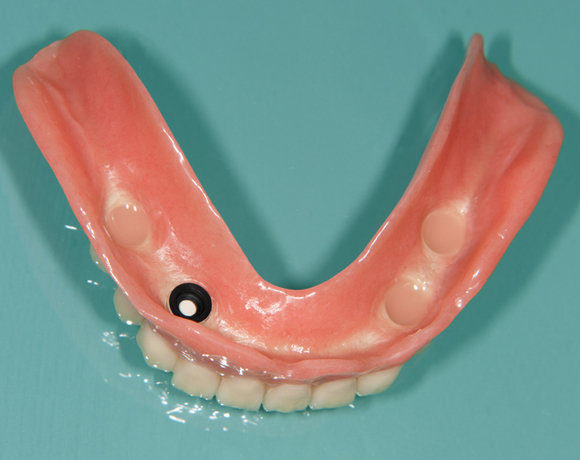

Fixierung einer Unterkiefervollprothese mit vier Implantaten

Mit Implantaten und dem Locatorsystem lassen sich Prothesen gut fixieren und geben einen guten Halt zum Essen und Sprechen

61 jähriger Patient, im Ober- und Unterkiefer mit Vollprothesen versorgt. Der Patient litt darunter, dass seine Unterkieferprothese keinen richtigen Halt hatte. So wurde ihm vorgeschlagen mit vier Implantaten und dem Locatorsystem die Prothese am Unterkiefer zu fixieren und damit einen hohen Komfort beim Essen und Sprechen zu ermöglichen. Der Patient entschied sich für eine metallfreie Versorgung. Es wurden Zeramex® P Implantate von Dentalpoint AG verwendet, für die Matrizen das System der Fa. Valoc das Novalocsystem gewählt. Die Verstärkung der Prothese wurde metallfrei mit einem PEEK – Gerüst gewährleistet.